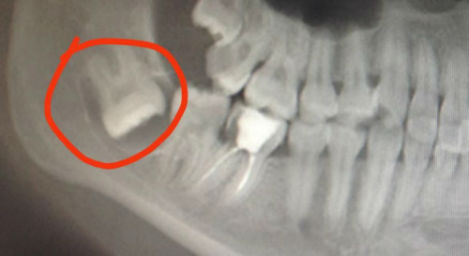

新疆網(wǎng)訊(記者吳治杰)近日,50歲張先生頜面部突然腫脹,吃了幾天藥不見效果于是來到烏魯木齊市口腔醫(yī)院就診,經(jīng)過X光拍片發(fā)現(xiàn)是牙源性頜骨囊腫,需要手術(shù)拔除埋藏在頜骨里數(shù)十年的一枚牙齒。

深埋阻生牙x光片

頜骨里為何藏著有牙齒?依沙克江告訴記者,不少復(fù)雜阻生牙深藏在頜骨里,由于被骨組織包裹,無法正常向上萌出,便橫向生長。有的就會形成頜骨囊腫,引發(fā)各種牙齒健康問題,有的甚至?xí)D破臨牙,造成更嚴(yán)重口腔問題。這種深埋復(fù)雜阻生牙,不通過醫(yī)學(xué)檢查發(fā)現(xiàn)不了,所以很多人并不知道自己頜骨里還藏著牙齒。